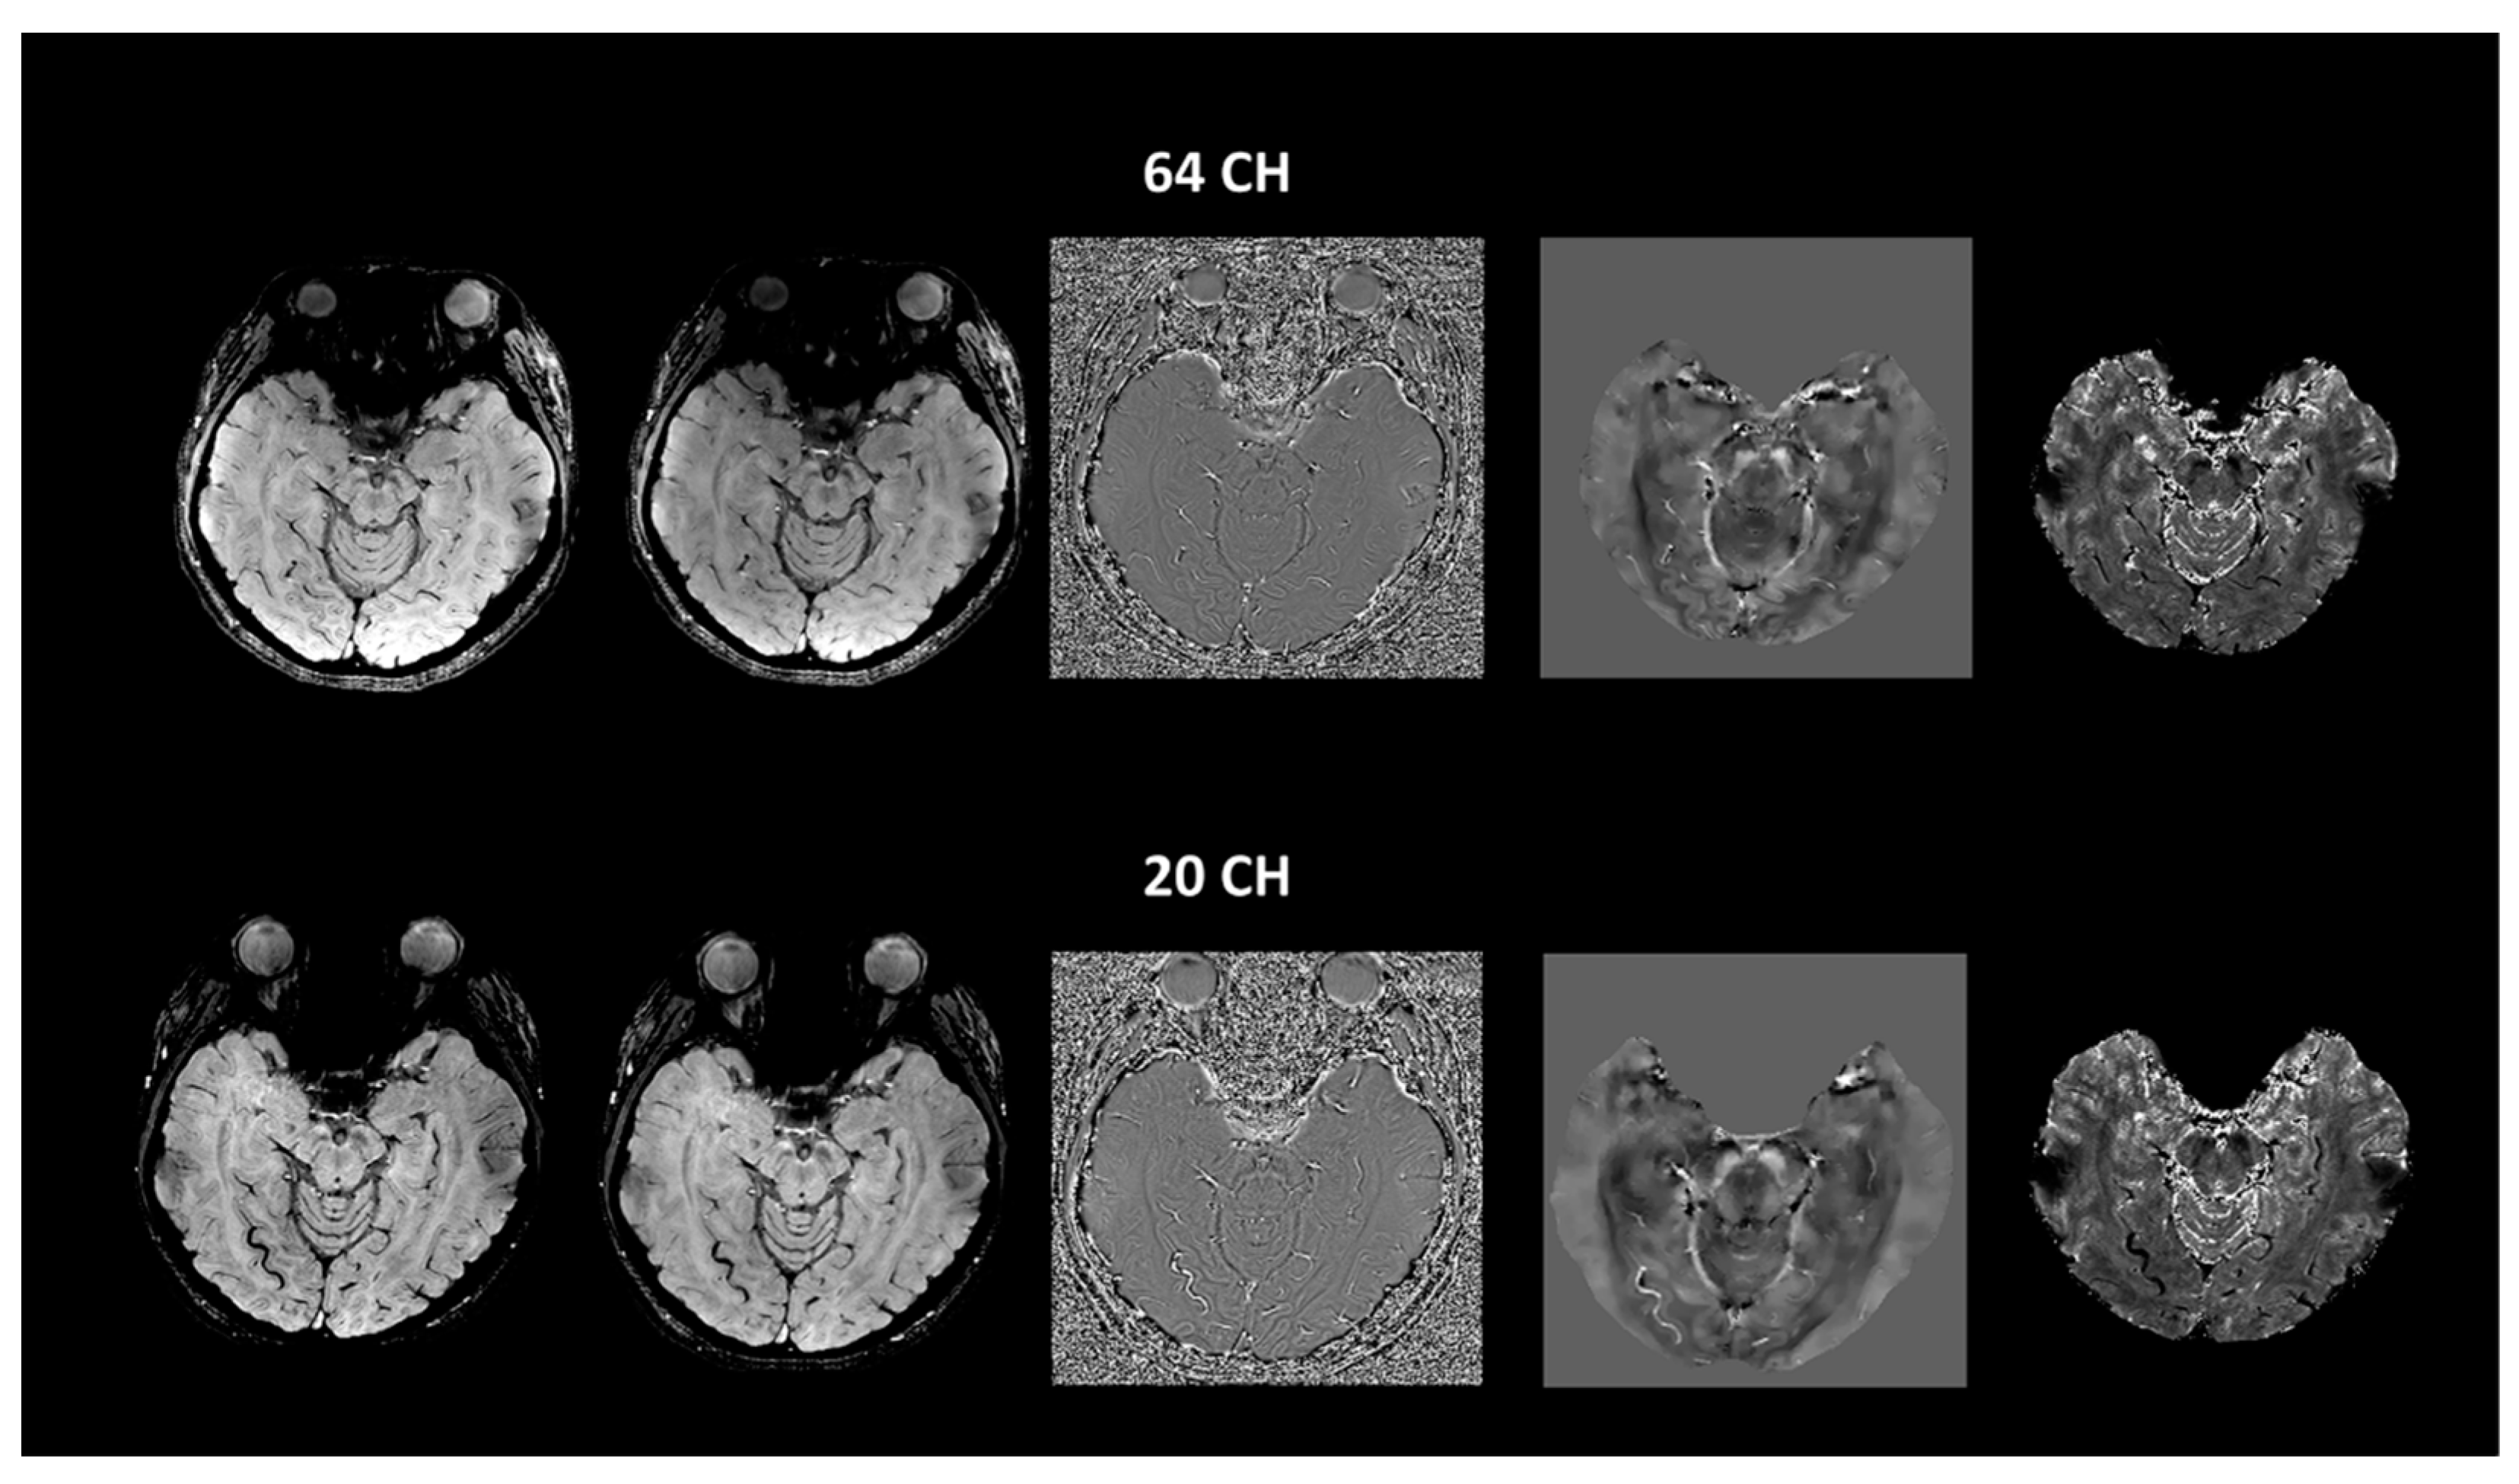

2.2. Imaging Protocols

2.3. Imaging Data Analyses

3. Results

4. Discussion